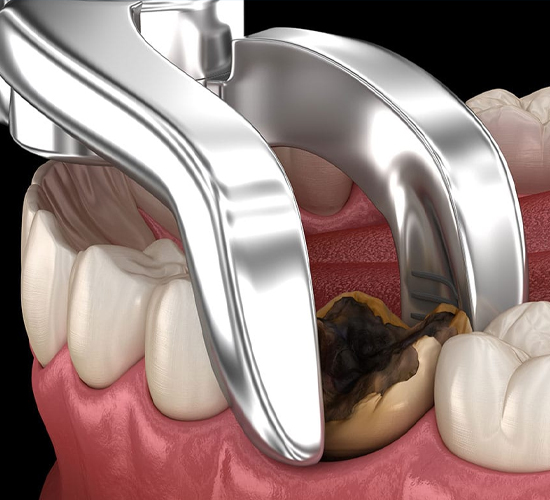

One of the most common dental procedures, a tooth extraction can eliminate bacteria and improve your overall oral health.

Makes an incision in the gum tissue to expose the tooth and bone, Removes bone that blocks access to the tooth root